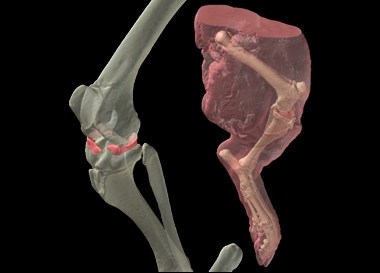

Using this composite MR dataset, the medial and lateral menisci of the knee were "segmented", or selected, from the MR data, as were the knee ligaments (not shown). The bones of the hindlimb were segmented from the CT data, and rendered in 3D (Figure 4). Because the bone and menisci are from two separate data sets (CT and MR, respectively), it was necessary to register the two datasets in order to put them into the proper anatomical position. Fortunately, Amira 3.1 has an auto-registration function allowing the user to automatically register the MR and CT datasets once they have been grossly aligned. After the two datasets have been registered, the resulting registration parameters can then be applied to the 3D model of the menisci that had already generated, and it slides right into the knee (Figure 4). |

To produce a single dataset from separate CT and MR volumes, we merged the two datasets. Since both datasets provide at least some information on similar structures (muscle, for example), we stripped away the redundant data. In other words, we removed all of the grey values that were less dense than bone from the CT volume (e.g., soft tissue, air), and from the MR volume we removed anything below the soft-tissue threshold (Figure 5). |

We then resampled, or resliced, the MR data set so that each slice in the MR volume corresponded directly to a slice at the same position in the CT dataset. Once this was done, we were able to merge the two datasets, which essentially blends a given CT slice with the corresponding MR slice. The result is a single dataset with bone from CT and the soft tissue from the MR.